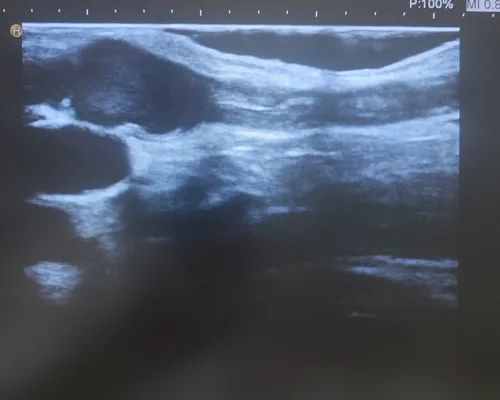

梁紅濤醫(yī)師檢查發(fā)現(xiàn)

董阿姨動靜脈內(nèi)

混雜高密度填充

內(nèi)瘺處震顫消失

多處狹窄、鈣化

一系列的問題表明

內(nèi)瘺堵了!